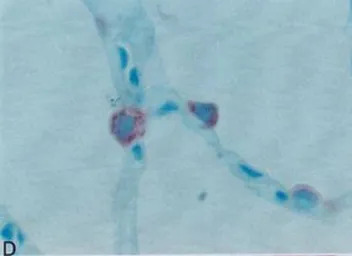

Paraffin-embedded sections of human lung immunostained with GTX60978